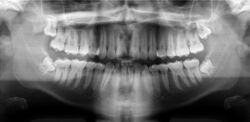

A basic panoramic radiograph